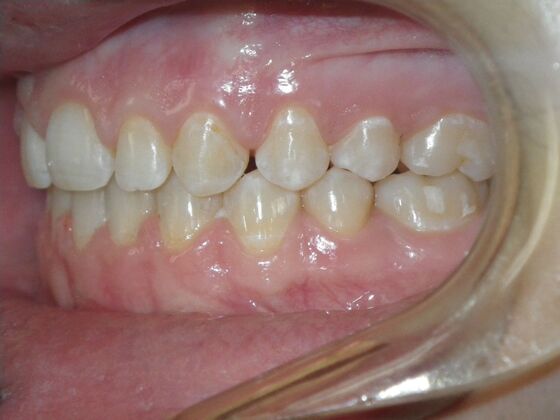

Patient presents desiring all spaces on upper and lower teeth closed. She will need slight expansion of upper arch due to lower molars leaning inward toward tongue. Used nitanium palatal expander with built in rotation of upper molars and lower lip bumper to upright lower first molars. Patient was also informed that her upper lateral incisors would require bonding due to their small size to close all space.